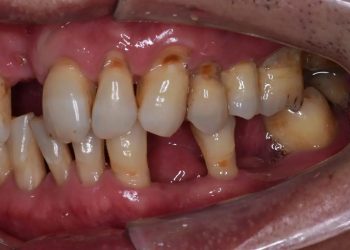

What Is Periodontitis? Understanding the Severe Stages of Gum Disease

Gum disease is one of the most common oral health problems that affect millions of people worldwide. If left untreated, ...